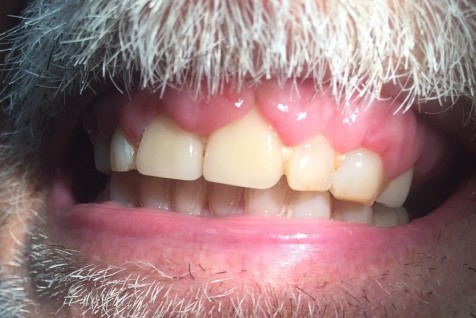

Gingival hyperplasia is an enlargement or overgrowth of the gum tissue, also known as the gingiva, around the necks of the teeth. It is an increase in the size of the gingival tissues and thus the term overgrowth is many times used in place of the term hyperplasia.

Gingival overgrowth can be caused by several mechanisms but will have very similar appearances. A study in the journal Histopathology describes the condition as "a small papillary or velvety bright red gingival overgrowth that bleeds easily." However, the overgrowth can be extensive and round in appearance. It is usually found on the front of the teeth and can be on the tongue side in some cases.

In the end, the overgrown gums may need to be surgically removed. The AAOM notes that good oral hygiene, especially the effective removal of plaque between the teeth, can alleviate the condition. In the case of drug-induced overgrowths, if patients are not able to discontinue the medication, surgical removal may be the only effective treatment. This can be done with a scalpel or laser.